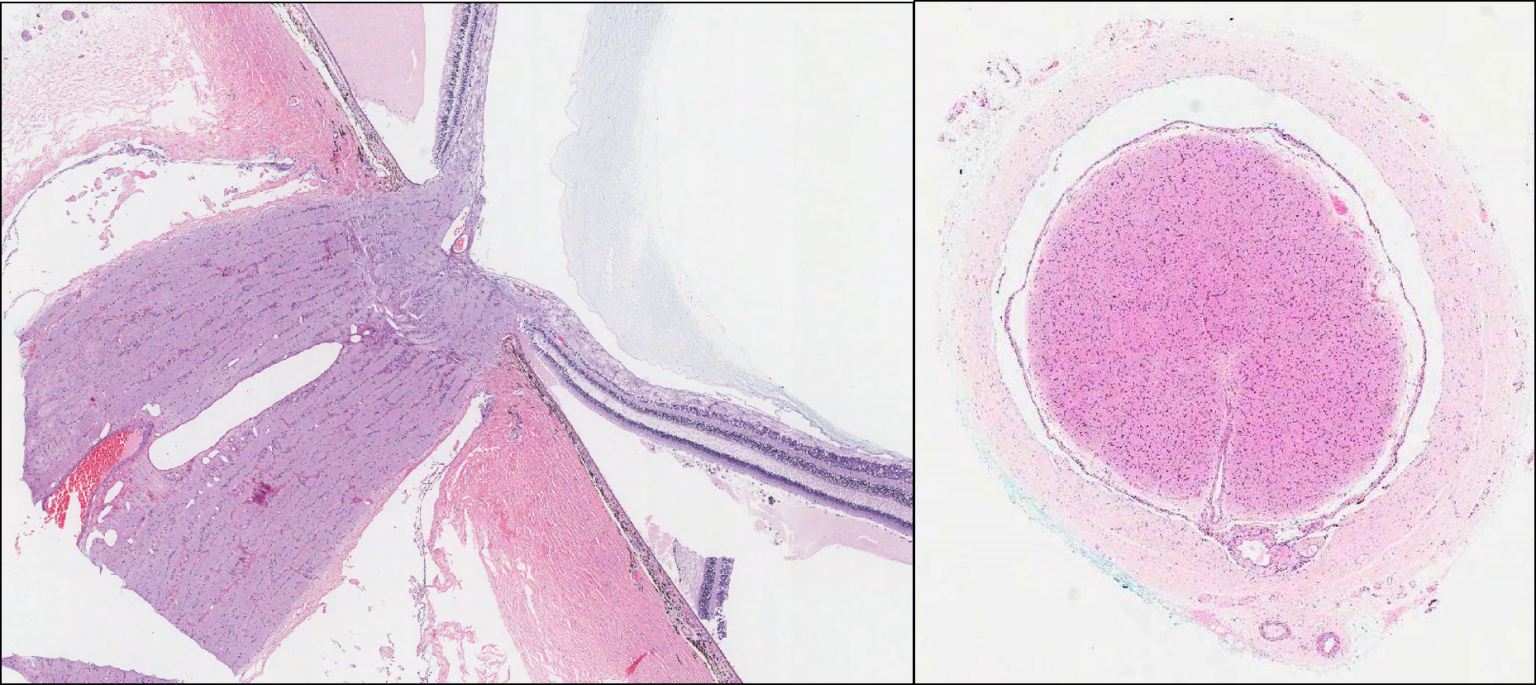

From medicine.nus.edu.sg

Eye Optic nerve NUS Pathweb NUS Pathweb Optic Nerve Eye Patch Optic neuritis (on) is a type of neuropathy (nerve disease) that can cause eye pain and vision loss or vision changes. Learn about this painful eye disorder that affects your optic nerve and what your doctor may recommend for treatment. Optic neuropathy occurs when this nerve is damaged, potentially affecting your vision quality and the amount you can see. It. Optic Nerve Eye Patch.

Eye Optic nerve NUS Pathweb NUS Pathweb Optic Nerve Eye Patch The optic nerve sends messages from your eyes to your brain so that you can interpret visual images. It happens when inflammation affects signals traveling. When the optic nerve is irritated and inflamed, it doesn't carry messages to the brain as well. Learn about this painful eye disorder that affects your optic nerve and what your doctor may recommend for. Optic Nerve Eye Patch.